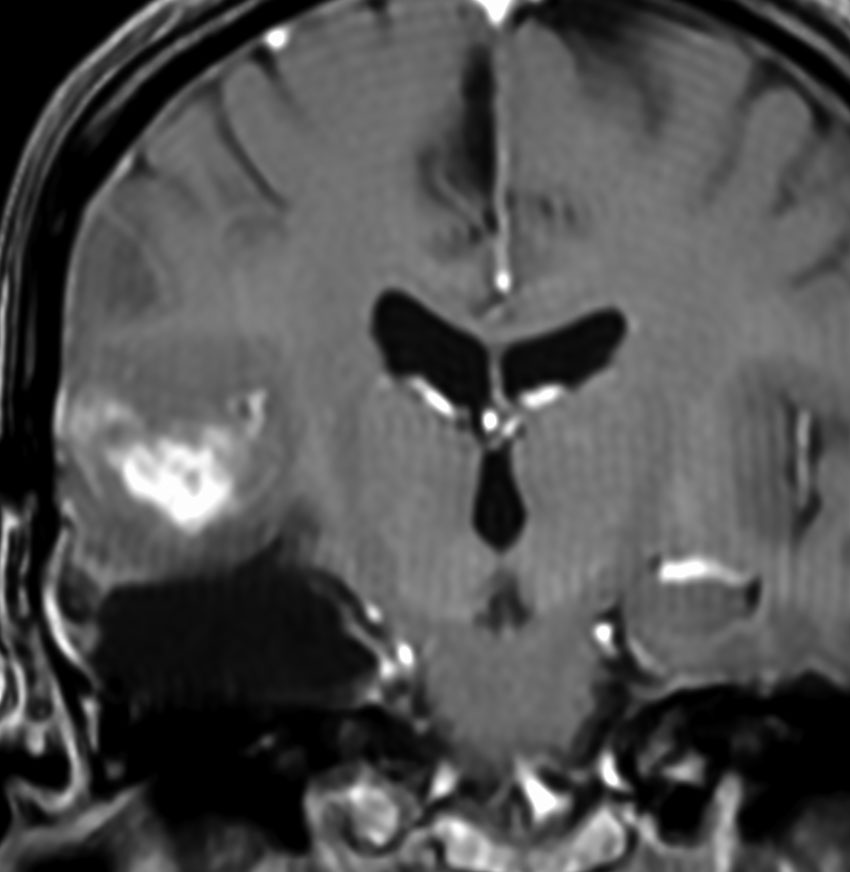

強直発作tonic seizureと夜間の嘔気発作で発症した女の子の乏突起星細胞腫です。海馬鉤と扁桃体を侵す内側側頭葉神経膠腫 mesial temporal gliomaと呼ばれる腫瘍です。特に小児に難治性てんかんを生じることで有名です。

T2強調画像とフレア画像でまだらな高信号を示しますが,境界は比較的明瞭です。限局性グリオーマ localized gliomaと呼ばれるタイプです。

CTでもMRIでも全く増強されません。

術後のMRIです。腫瘍は全摘できていて再発はありません。手術でとても大切なことは,てんかん原性のある海馬鉤の腫瘍を摘出するだけではなくて,扁桃体切除 amygdalectomyも加えることです。それによって症候性てんかんをmedication freeにもっていける可能性があがります。扁桃体は片側(この場合は左)切除しても症状は出ません。